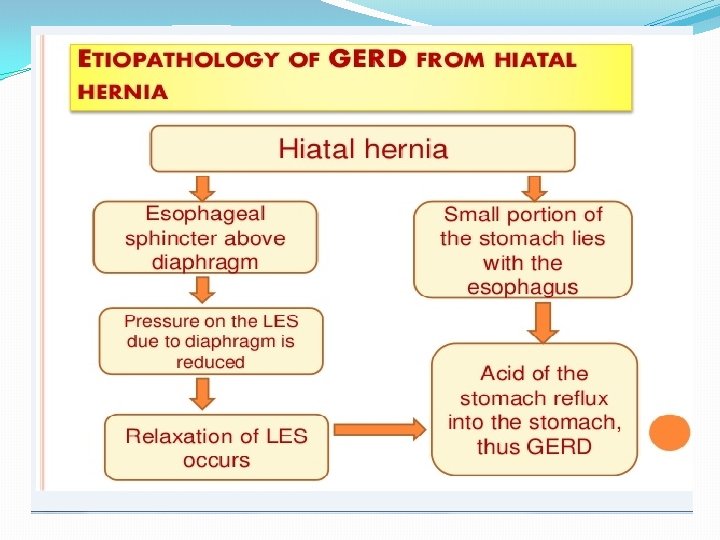

The mechanisms involved in the pathogenesis of GERD are multiple and include: 1. impaired LES resting tone 2. increased number of transient LES relaxations (TLESR) 3. Gastric distention (delayed gastric emptying, large fatty meals) can significantly increase the rate of transient LES relaxations) 4. hiatal hernia (promoting lower oesophageal sphincter dysfunction)